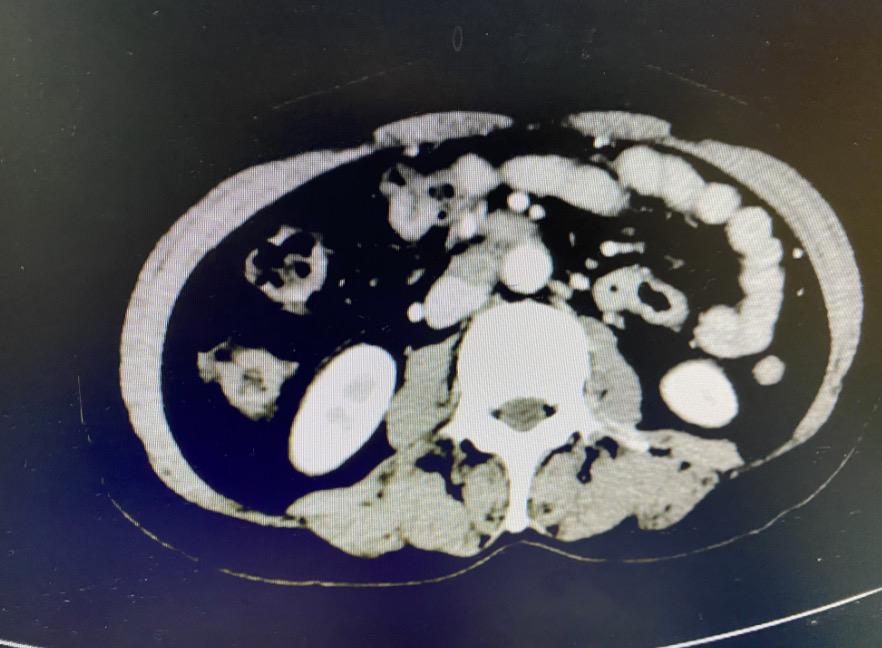

结合患者腹部CT等其他辅助检查结果分析手术,首先,患者病灶累及腹膜、肠管及膀胱,涉及多个重要脏器,范围非常广泛。其次,腹膜后可见多处肿物环绕腹主动脉及下腔静脉处,其中较大的融合淋巴结大小约7*3*2cm,紧密地贴在腹主动脉和下腔静脉之间,将下腔静脉挤压凹陷变形,像一颗“定时*弹炸**”一样,危及生命。如果进行手术治疗,切除所有病灶,达到R0水平,使患者疗效获益最大化,除了切除所有盆腔、腹膜及所涉及脏器组织外,必须切除下腔静脉旁的所有融合肿大淋巴结。

但切除下腔静脉旁融合肿大淋巴结谈何容易,下腔静脉是人体最粗大血管,主管身体循环的生命干道,静脉壁最薄,承受压力最小,直接汇入心脏,稍有不慎,特别是在下腔已被肿瘤组织环绕并挤压变形的情况下,一旦破裂出血会迅速危及生命,这个手术需要手术团队精湛的手术技巧和默契的配合。

探查腹膜后肿物时,大家都倒吸了一口凉气,只见巨大的融合淋巴结环抱在腹主动脉和下腔静脉之间,紧紧地贴在薄薄的下腔静脉管壁上,大血管壁吹弹可破,随时都有破裂大出血,危及生命的可能。肿物与下腔静脉间几乎无缝可插,且肿瘤糟脆,剔除过程惊心动魄。最终在王军主任、韩世超教授和张艳开老师的密切配合下,在心外科吴海波主任团队、麻醉科肖昭扬主任团队以及手术室宋军护士长团队的保障下,凭借精湛的手术技巧,手术团队的完美配合,这枚“定时*弹炸**”被完整切除,手术过程顺利,几乎无血化,手术室里每个悬着的心放了下来。术后患者安返病房,恢复顺利。